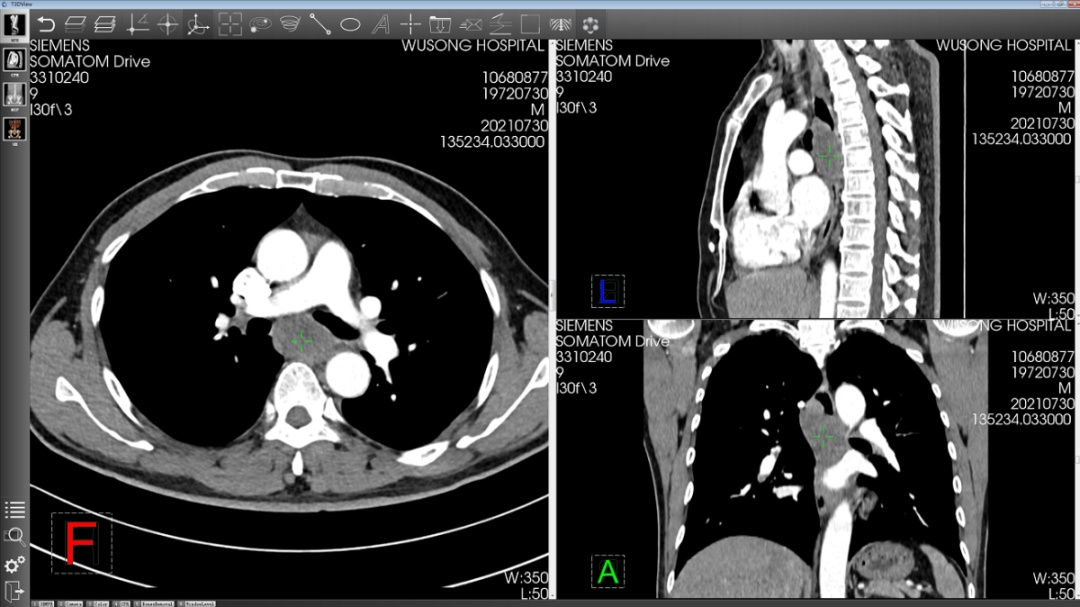

人体食道壁最厚的地方只有4毫米。而孙先生的这个食管肿瘤环绕着食管壁生长,非常巨大,而且形态不规则,紧邻着心脏、胸主动脉和气管。在如此狭小的空间进行手术,就像在瓷器店里抓老鼠一般困难。

手术中,周平红教授手法精准,沿着病灶周边用内镜刀一点一点切割,最终耗时46分钟,将一个8.5厘米*4厘米大小的肿瘤从食管壁完整剥离。这个好消息让守在一旁的家人如释重负。

于是,一家人来到复旦大学附属中山医院吴淞医院求医。对于这类疑难病症,医院立即启动专家会诊,经过周密分析,专家团队决定采用经内镜黏膜下隧道肿瘤切除术切除肿瘤,不用开胸,也不用切开食管。

手术运用的在食管壁内打“隧道”的方法,正是周平红教授的独创技术。与传统开胸手术相比,这个内镜微创手术时间短、创伤小、痛苦小、费用低、恢复更快。